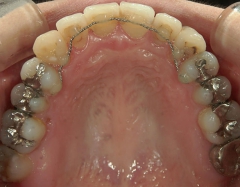

矯正_灰色.pngno.7_6967_治療前_上_01.jpg矯正_灰色.png

矯正_灰色.pngno.7_6967_治療後_上_01.jpg矯正_灰色.png